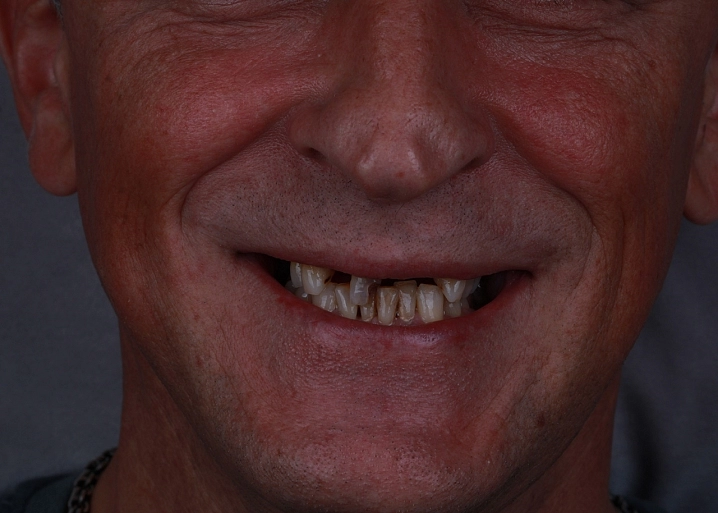

Показанием к проведению открытого синус-лифтинга является высота костной ткани менее 6 мм в области зубов, примыкающей к гайморовой пазухе. При открытом синус-лифтинге производится разрез слизистой, отслаивается слизисто-надкостничный лоскут, в передней стенке пазухи формируется перфорационное отверстие. Далее отслаивается слизистая самой пазухи, укладывается костный материал, после отверстие перекрывается специальной мембраной и слизисто-надкостничный лоскут ушивается.